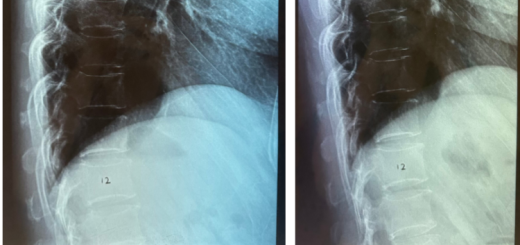

Reversal of L5 and L4 Disc Degeneration